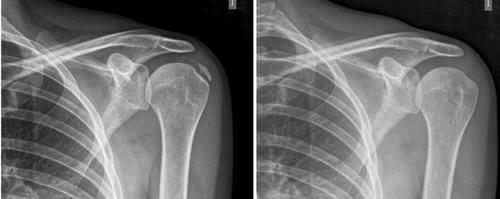

Figura 1

Figura 2